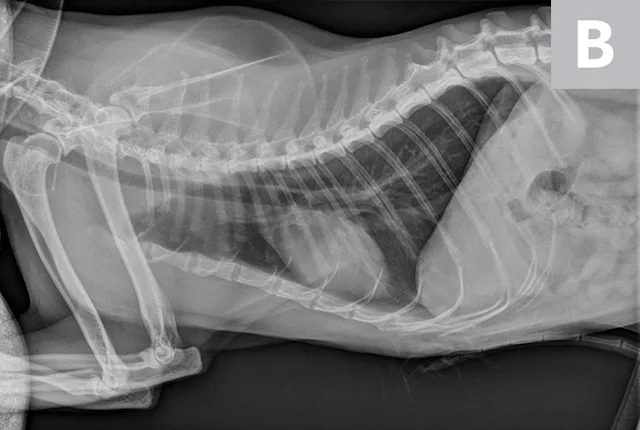

Thoracic radiographs are generally difficult to assess in cats due to age-associated variability. The cardiac silhouette develops increased sternal contact as cats age (Figure 1), with the aorta creating a notch or right-angled appearance that can falsely suggest left atrial enlargement on ventrodorsal projection. The aortic arch may have a rounded appearance on the ventrodorsal projection that can be mistaken for a pulmonary nodule in the left cranial lung lobe (Figure 2).1

FIGURE 1A

Lateral radiographs of a 2-year-old cat (A) and a 9-year-old cat with increased sternal contact of the cardiac silhouette (B).